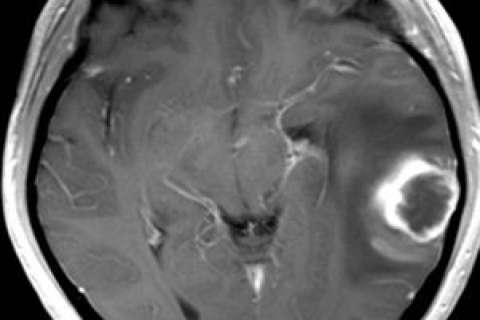

Dr. Whitney Pope is interested in the molecular imaging of gliobastoma multiforme and the imaging and molecular diagnostic strategies in the prognosis and management of gliomas.